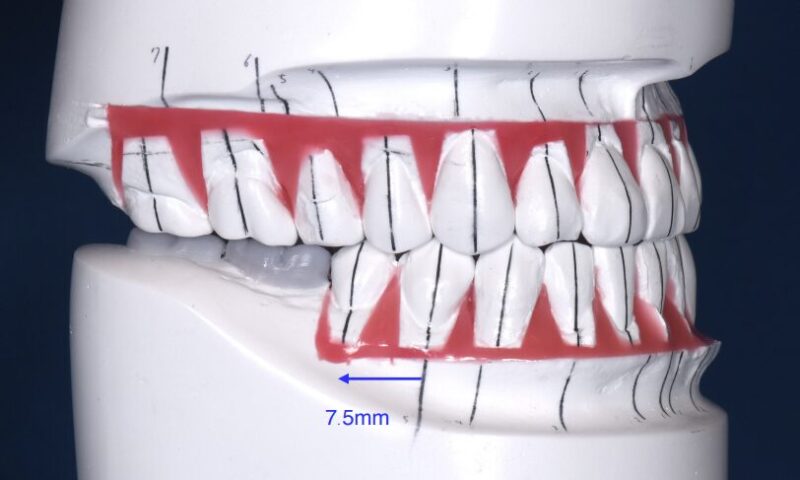

この場合、インプラントを先に行い、奥歯の噛み合わせを安定させてから矯正を行うことが重要です。一方で、こちらのケースでは理想モデルを組んだ結果、矯正で歯を動かす量が大きいことが判明しました。

もし思うように歯が動かなければ、先に入れたインプラントが周りの歯と大きくずれる危険性があります。そこで今回は細くて簡単に埋めたり外したりできる仮インプラントを利用しました。(図6)

仮のインプラントの上に仮の歯を装着して矯正治療を行い、矯正後に仮のインプラントを外して正規のインプラントを入れました。